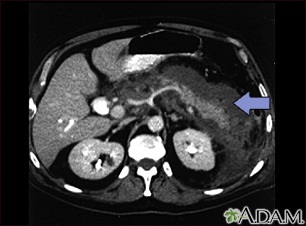

This upper abdominal CT scan shows inflammation and swelling of the pancreas caused by acute infection (pancreatitis).